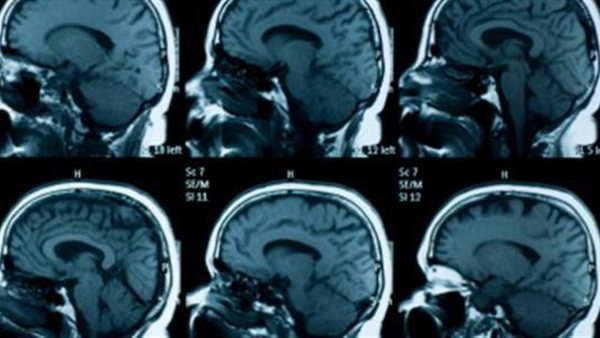

استغاث محمود نويري بالإسماعيلية، ووالد 3 أطفال لعلاج أبنائه المصابين بضمور في المخ، حيث يخضعون لجلسات علاج طبيعي، بالإضافة إلى حاجتهم لإجراء عدد من العمليات العلاجية.

وأضاف محمود أنه بدأ في البحث عن أطباء متخصصين، بعدما لاحظ بعض الأعراض التي ظهرت على ابنه عندما بلغ 6 أشهر من عمره، حيث تم تشخيصه بمرض ضمور المخ، وذلك بعد معاناة طويلة خاصًة أن كل التحاليل الخاصة بالطفل قبل ولادته سليمة.

وذكر أن الأطباء أخبروه بأن ضمور المخ ليس له علاج قاطع، ولذلك سيتم علاج الأعراض، بمعنى معرفة الأجزاء والأعضاء التي أثر عليها الضمور وسيتم علاجها، وبالفعل بدأ طفله بتناول جرعات العلاج الموصوفة من قبل الطبيب.